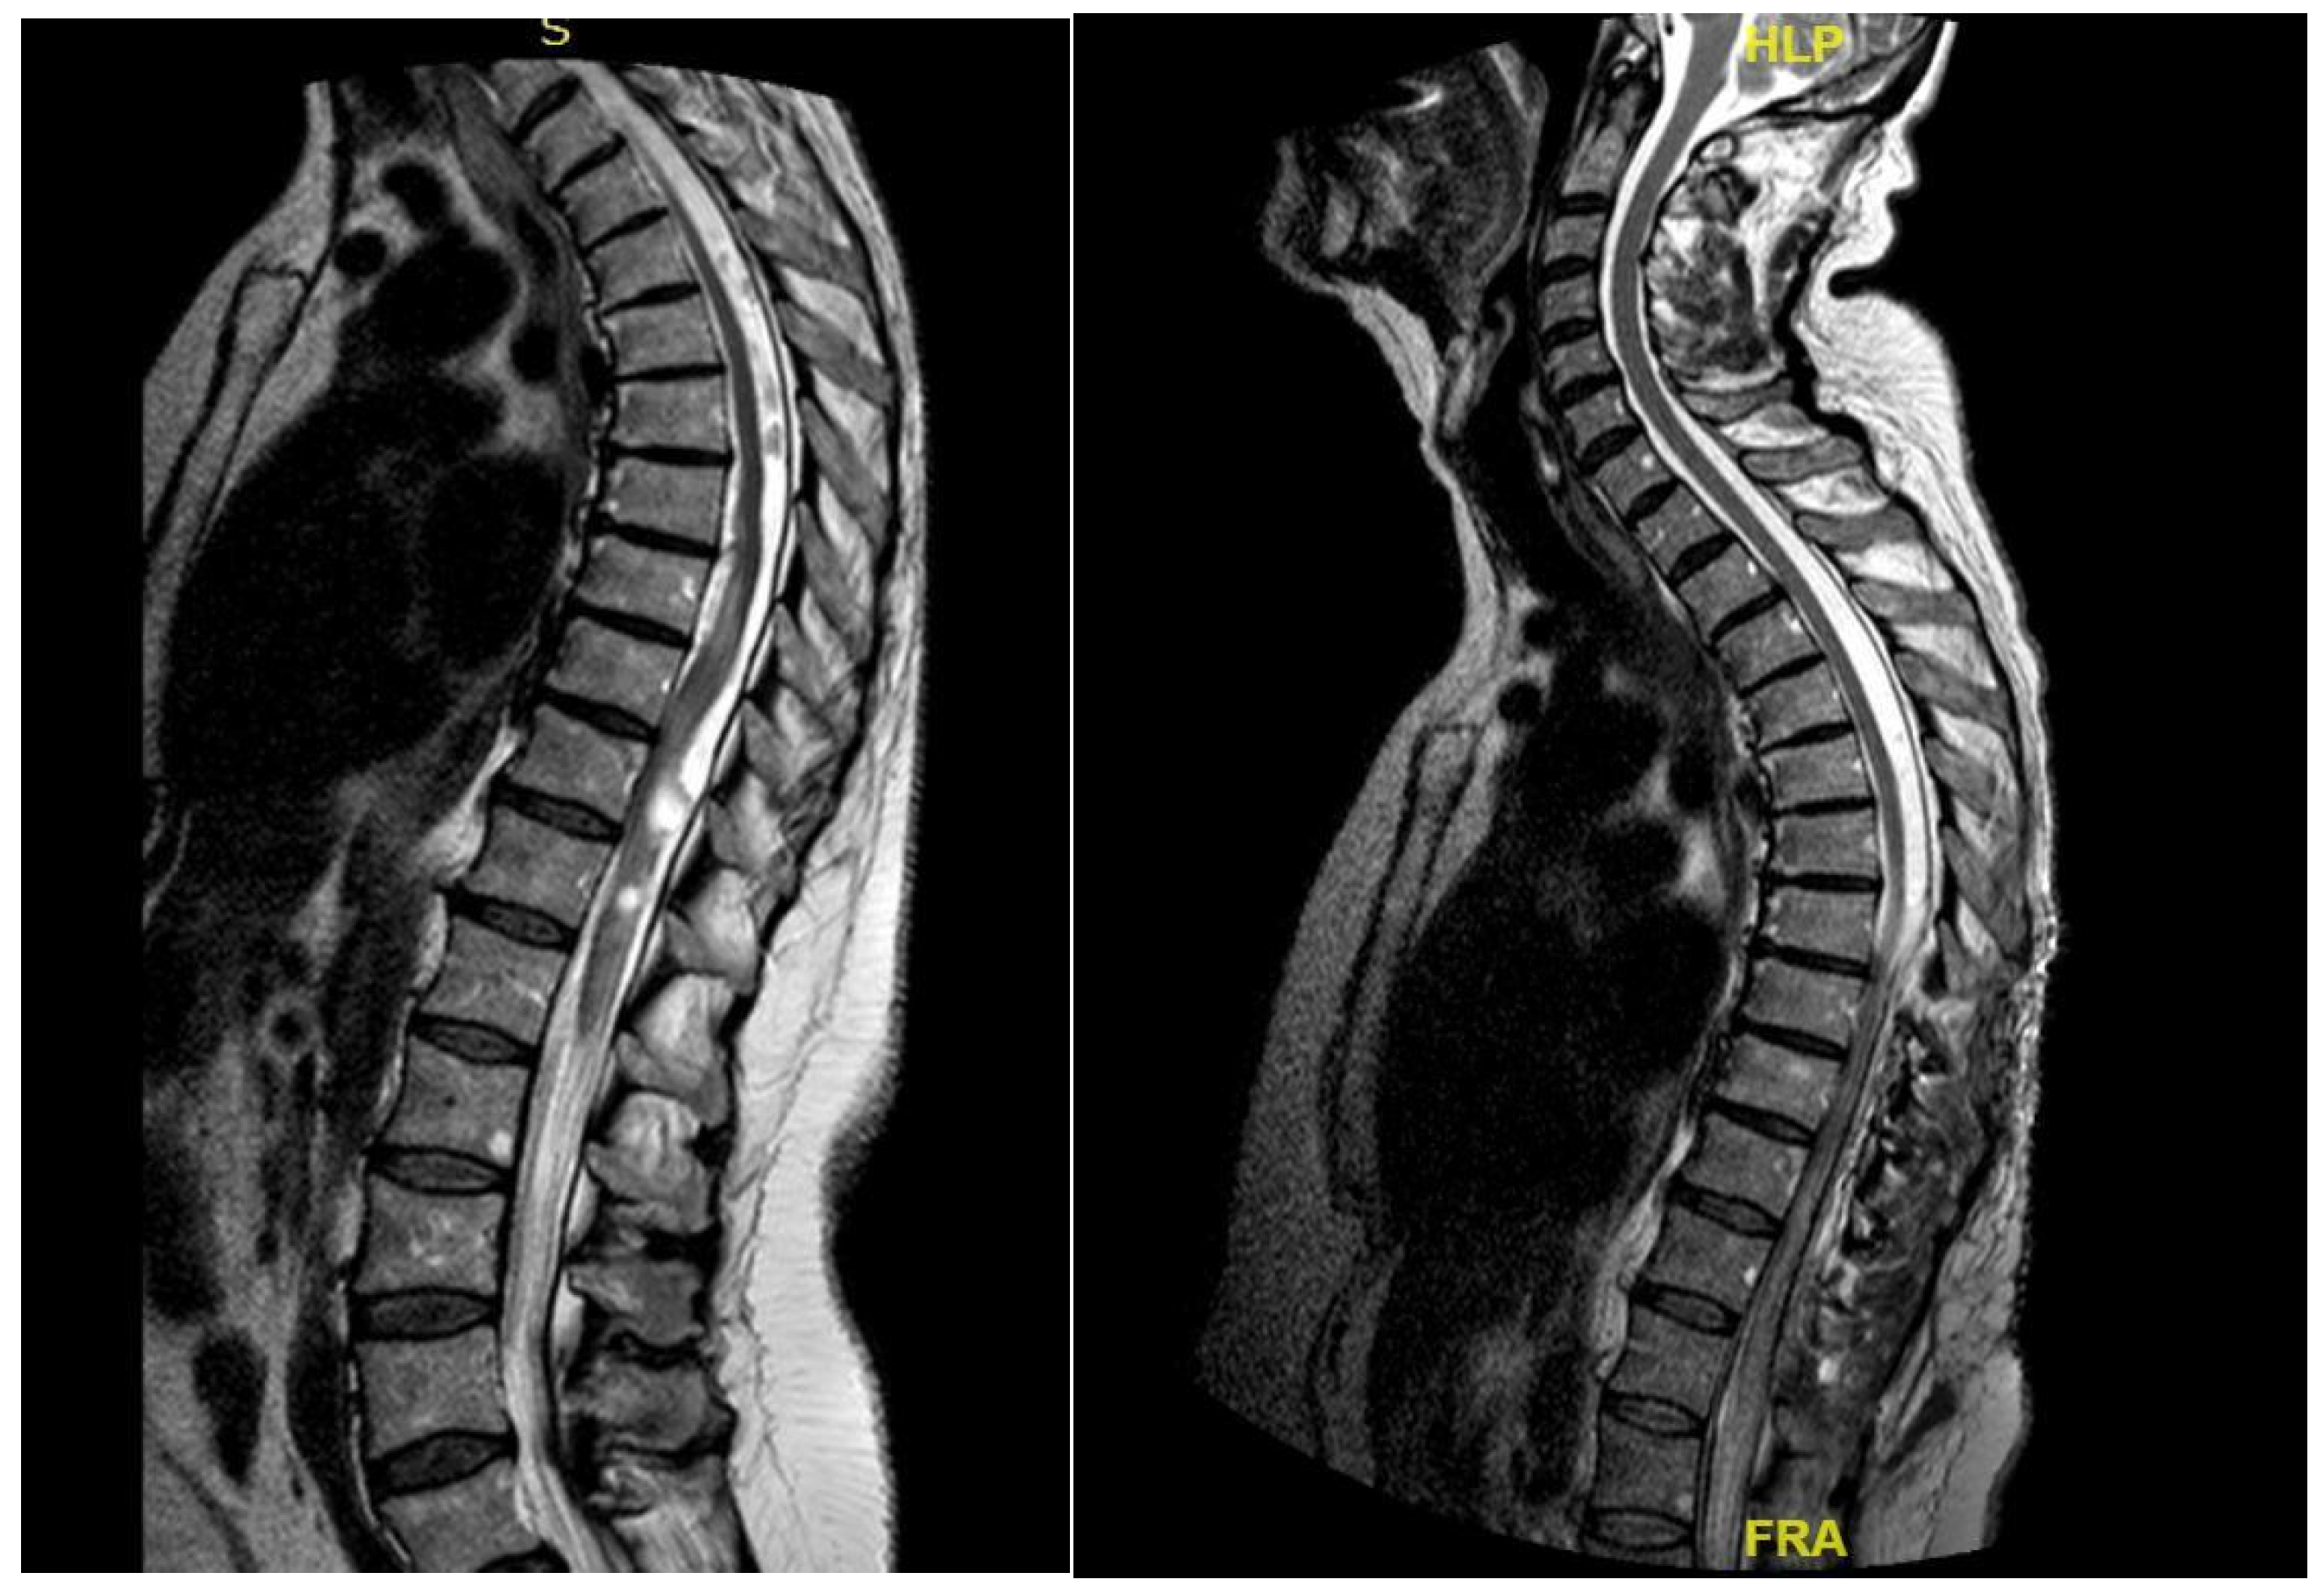

3.4.3. Case 3

3.4.4. Case 4

| Level | T12–L2 | C5–C6 | T7–T10 | T8–T9 | T8–T11 |

| Location | Intramedullary | Intradural | Intradural–Extradural | Intramedullary | Intradural |

| Surgical treatment | lysis of adherences and syrinx cavity opening | resection of the cystic formation and adhesiolysis | resection of the cystic formation and adhesiolysis | resection of the cystic formation and adhesiolysis | resection of the cystic formation and adhesiolysis |

| KPS pre-op (%) | 70 | 50 | 70 | 80 | 90 |

| KPS post-op (%) | 80 | 50 | 60 | 90 | 80 |

| ASIA score pre-op | C | B | B | C | D |

| ASIA score post-op | D | B | C | C | D |